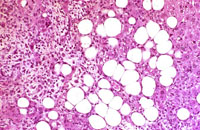

An Ito cell tumor that has replaced much of the normal hepatic parenchyma without distorting the normal contour of the liver; higher magnification shows fat-filled and stellate cells in the hepatic sinusoids.

The proliferating stellate cells have a myxomatous appearance in some areas and have caused atrophy of hepatic cords.